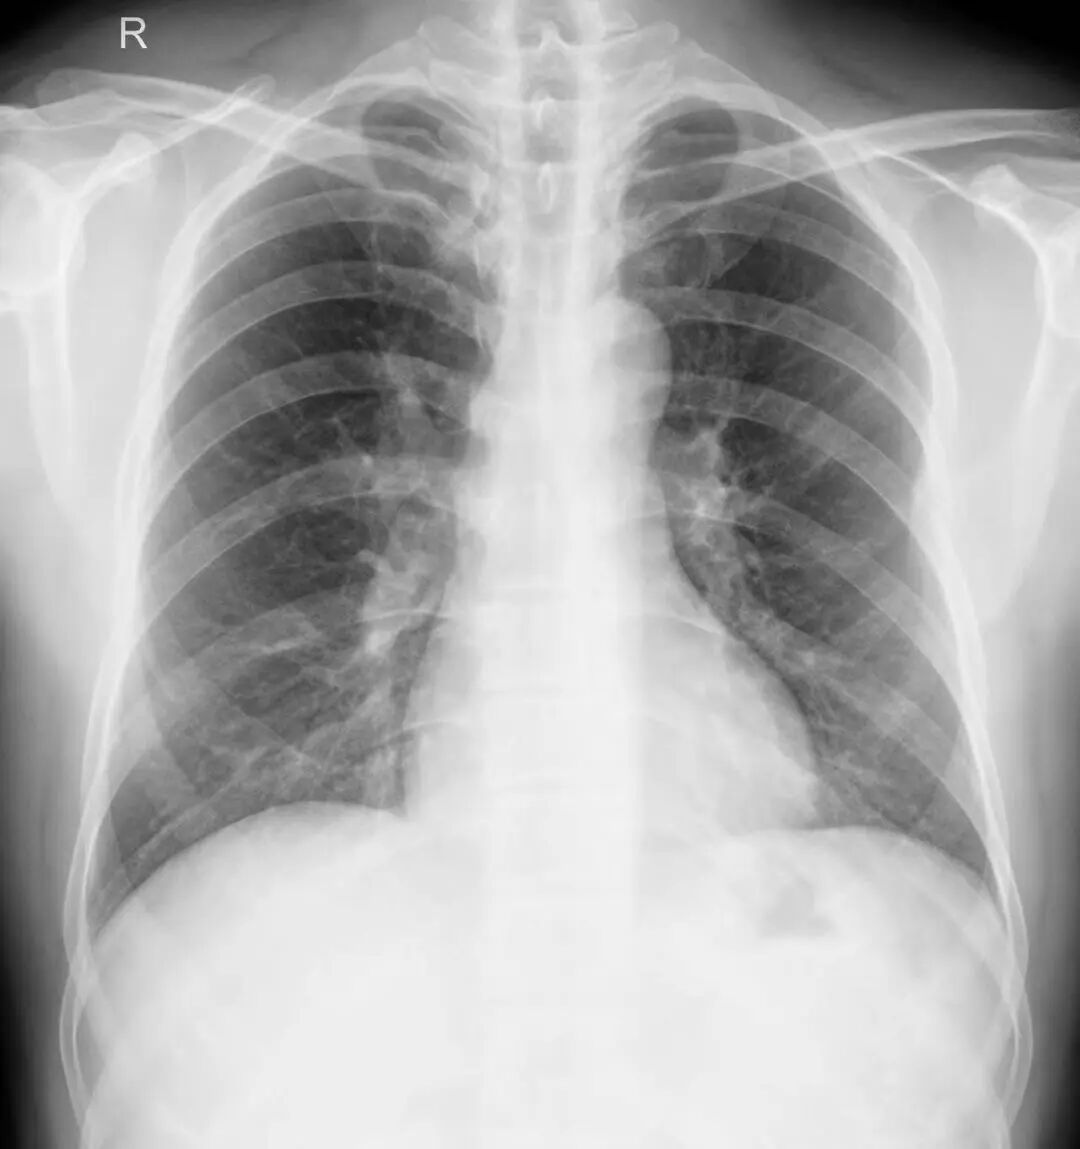

案例1、3岁的患儿平片未能明确显示肺部炎症,CT扫描显示双肺多发炎症。